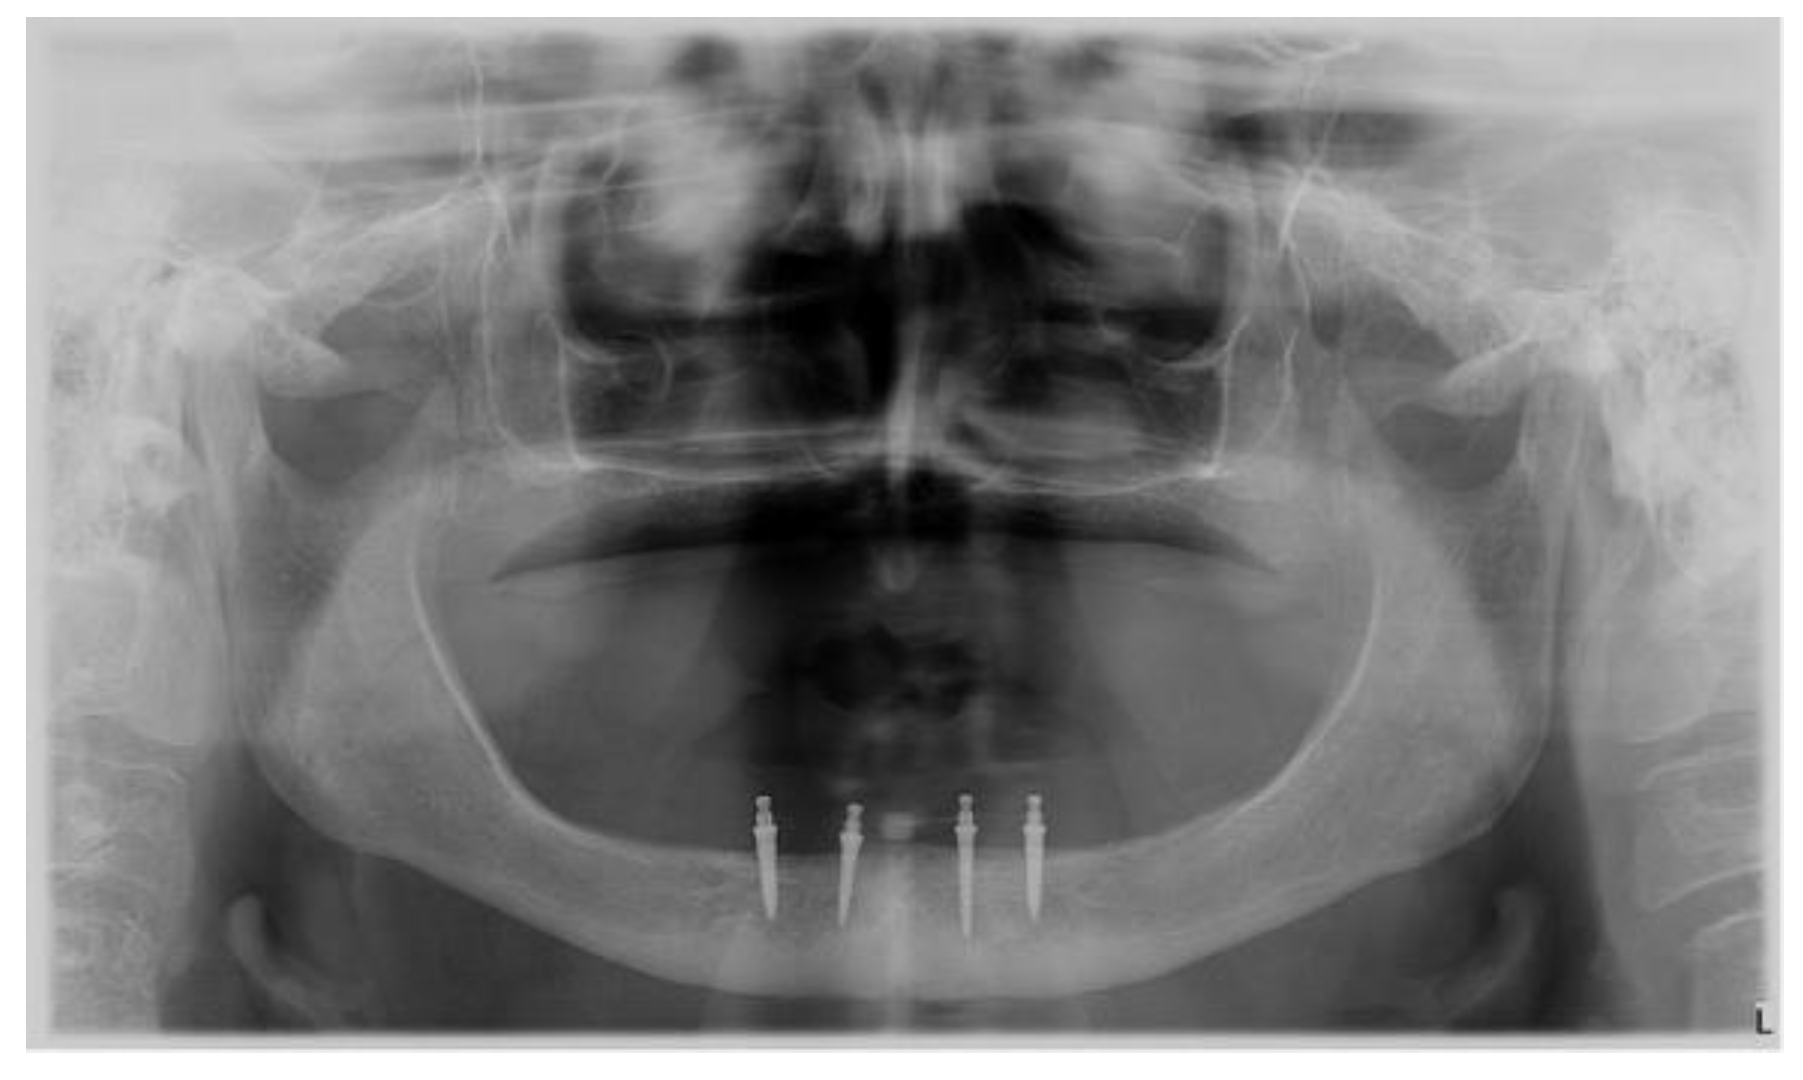

2. Case Report